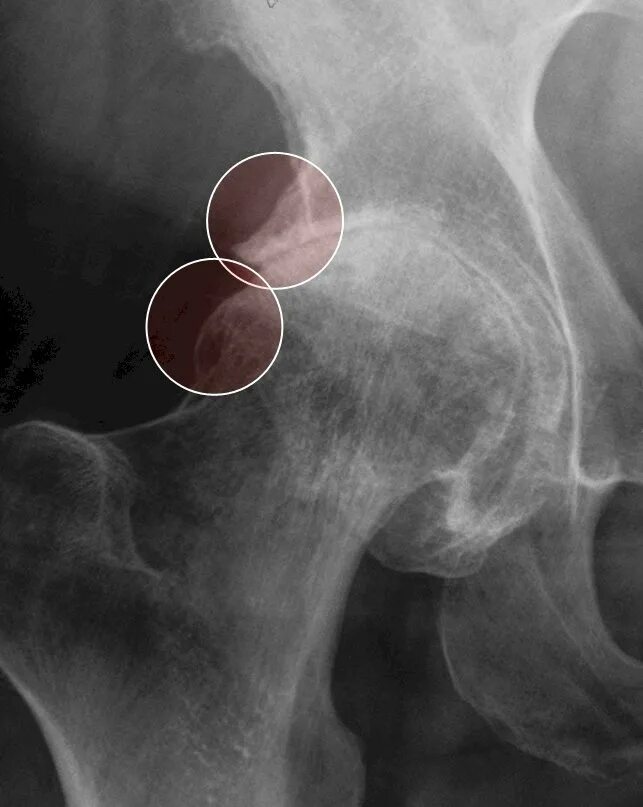

Остеофит симптомы